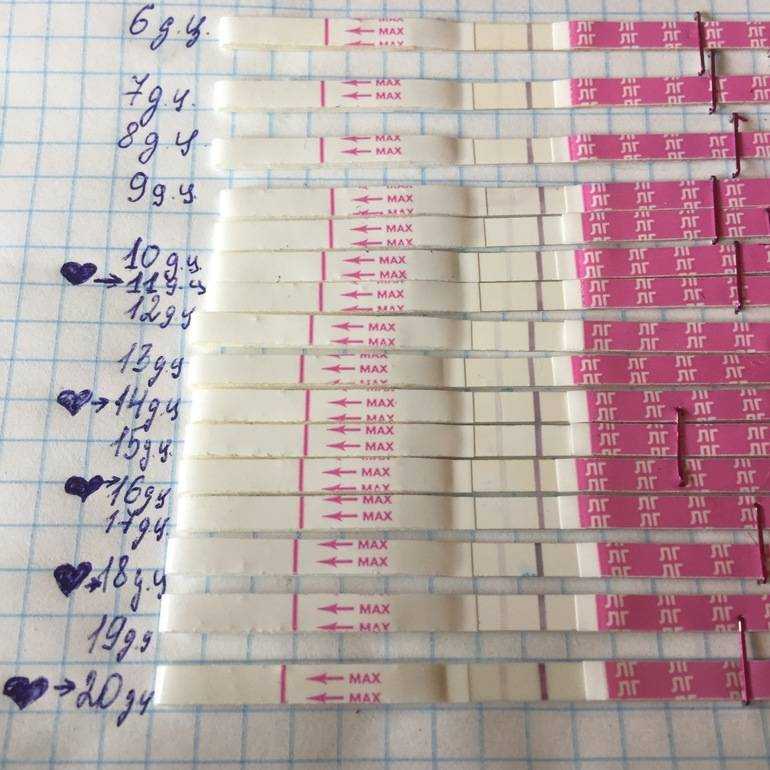

Рекомендации по зачатии